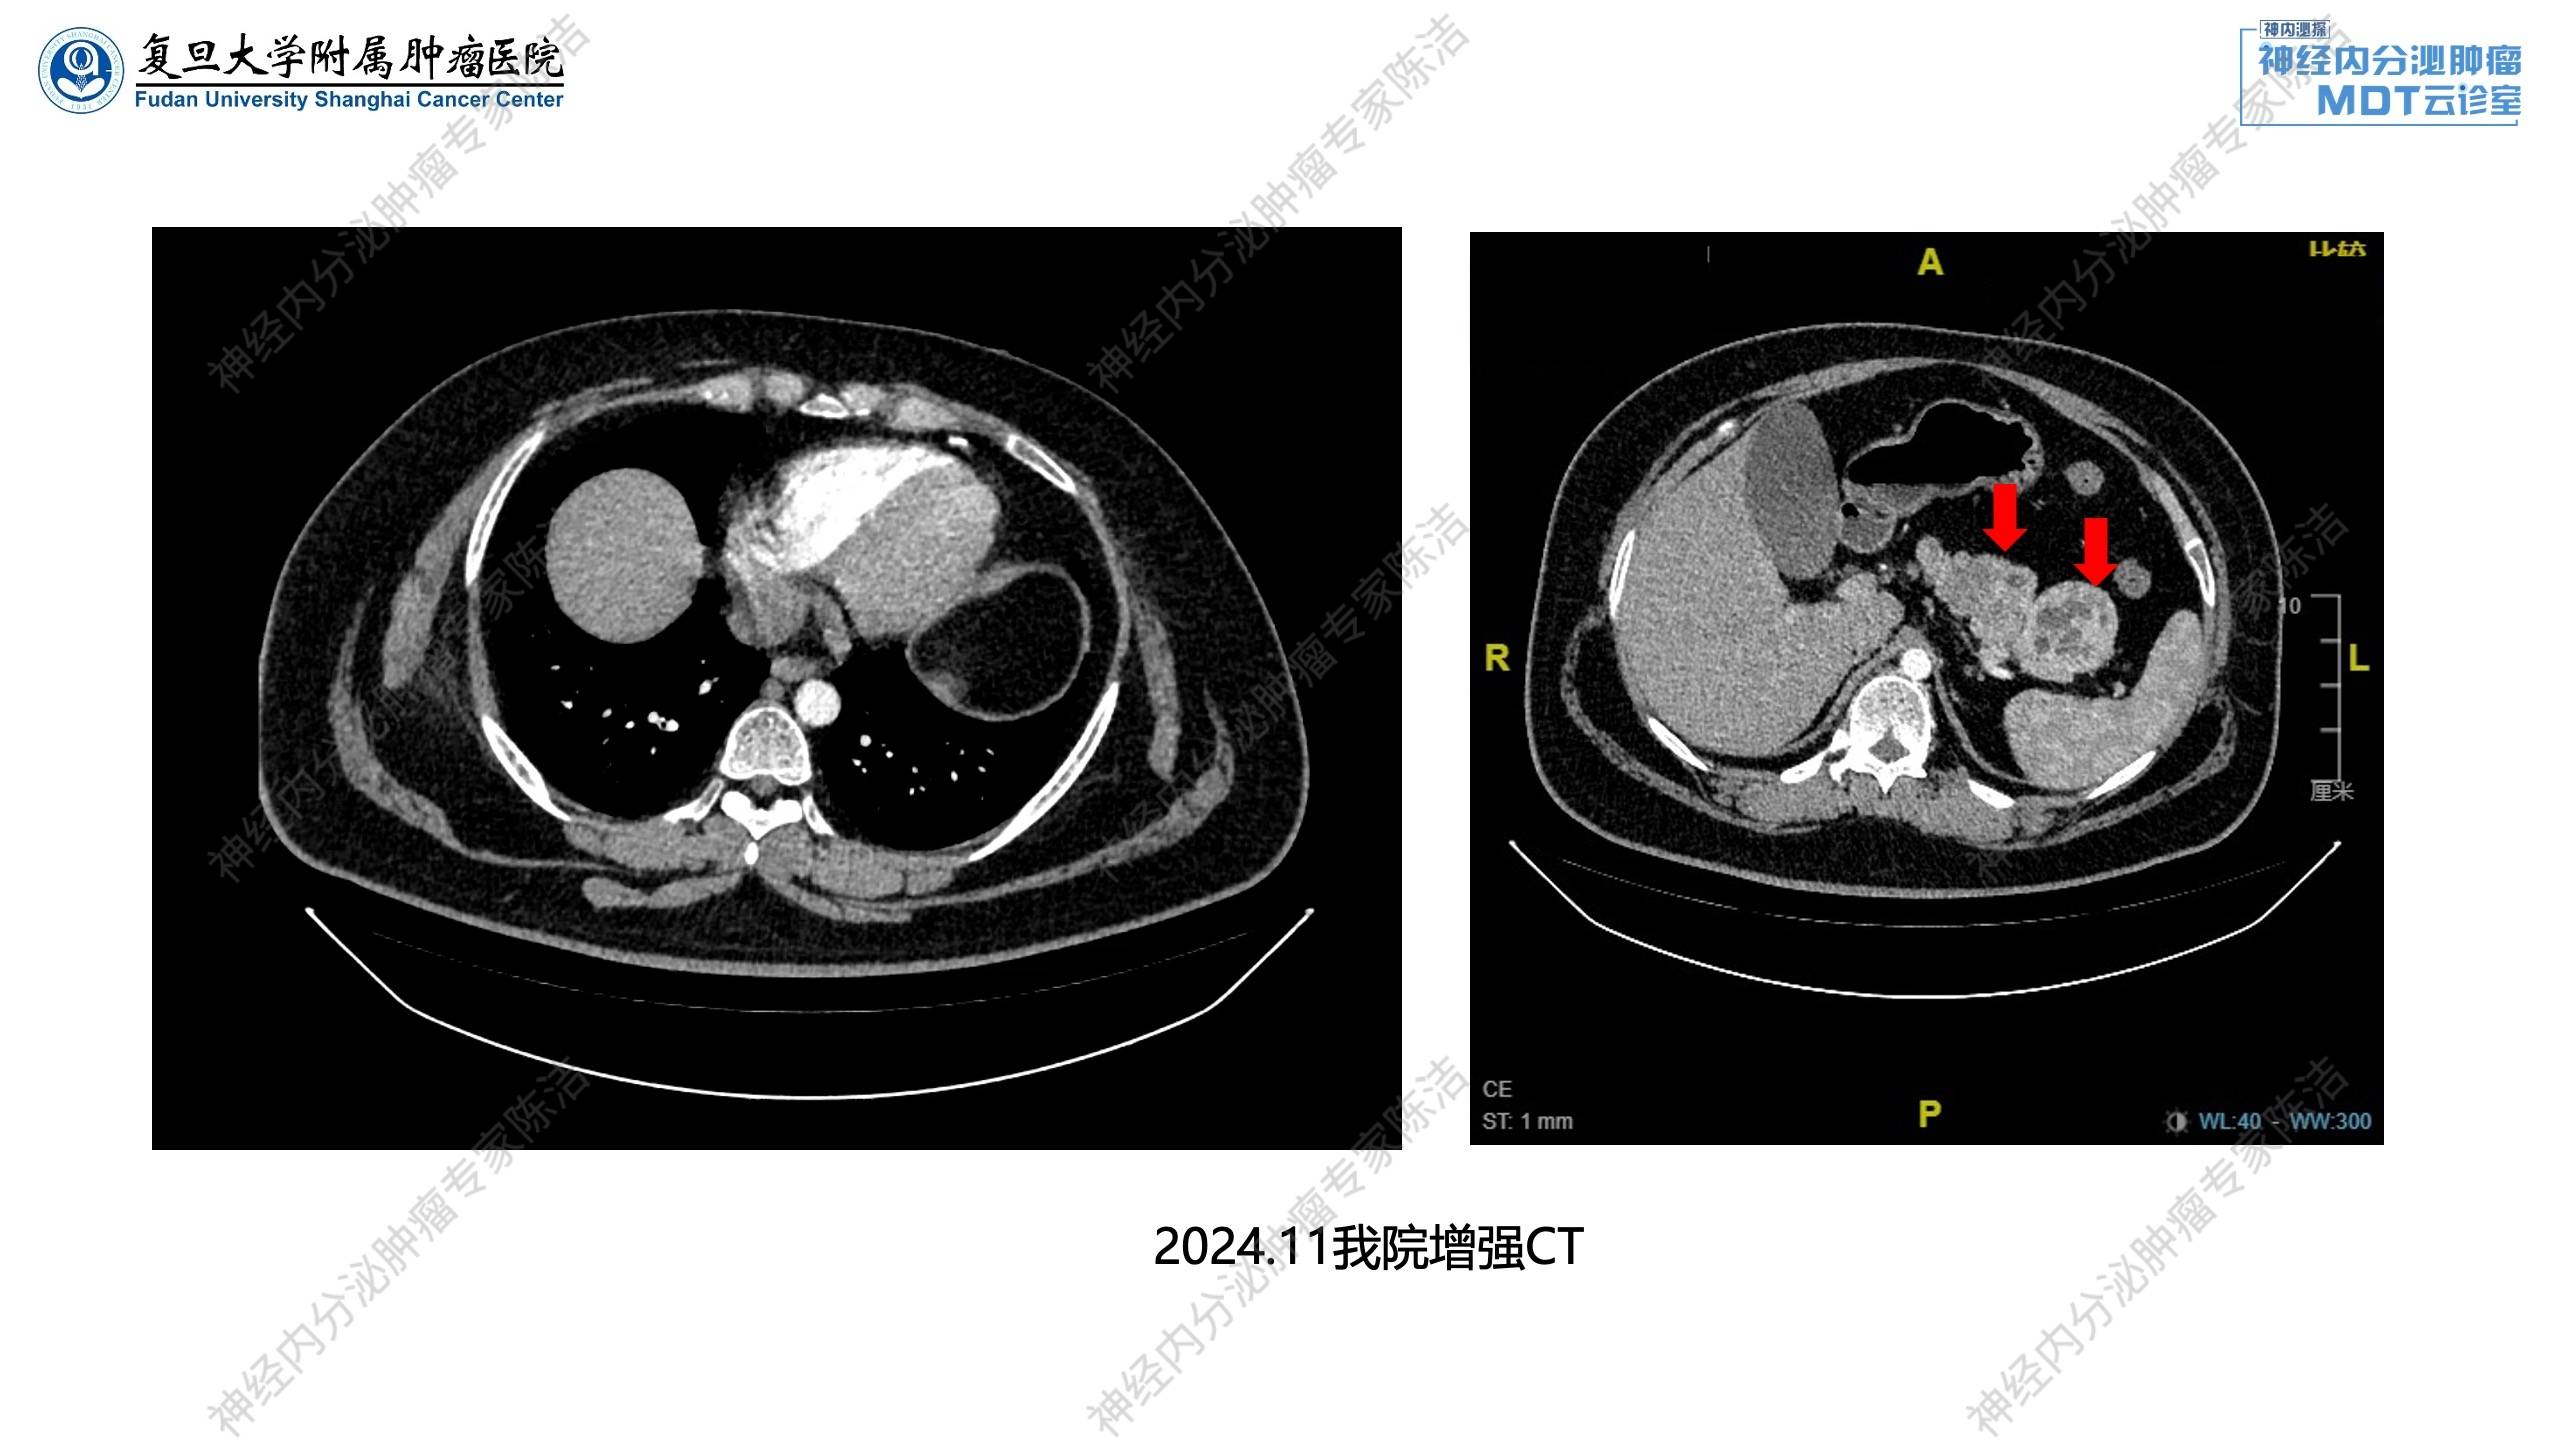

2024年11月:予完善相关激素检测,示垂体激素正常;胃泌素升高,PTH升高,血钙轻度升高。增强CT示胰腺多发囊实性占位;双肾小结石。

放射诊断科汤伟教授:腹部增强CT显示胰体部有一个比较大的富血供占位,中央伴有一些囊变。除此之外,胰头、胰体、胰尾还有多个富血供占位。这跟第一个病例比较相似,为多灶性胰腺神经内分泌瘤的改变。